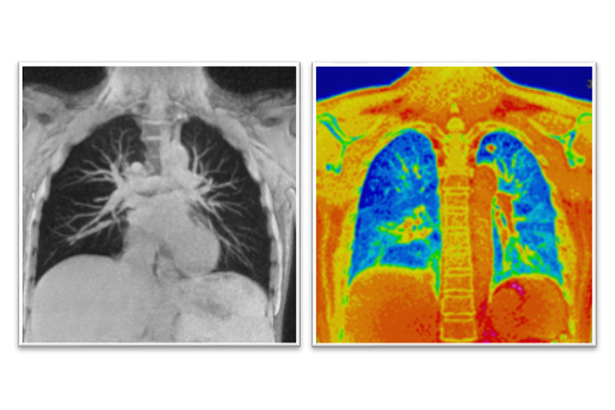

結合UTE序列和純源射頻,Galan 3T可提供高清MR肺部成像,無創(chuàng)無輻射評估肺實質及功能改變,對肺部疾病的早期篩查、鑒別診斷、治療及療效評估具有臨床價值。